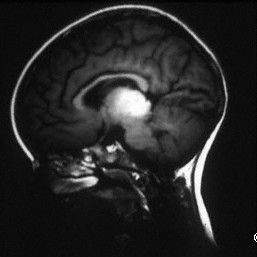

Pinealoma associated with a bilateral retinoblastoma

MRI SAGITTAL SECTION demonstrates massive extrascleral tumor extension (T).

Choroidal Melanoma

Choroidal Melanoma - MRI CORONAL section demonstrates massive extrascleral tumor extension (T).